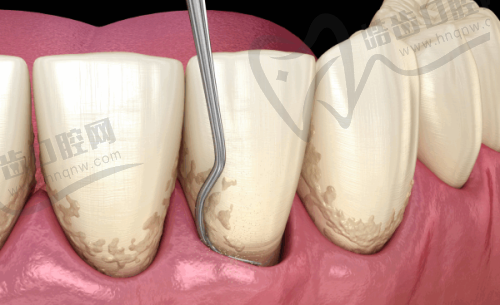

广州牙德堡口腔398元起深度洁牙套餐 超声波+喷砂抛光 告别烟渍茶渍

你是否还在为牙齿上的烟渍、茶渍而烦恼?想要拥有一口洁白干净的牙齿却又担心价格太贵?现在,广州牙德堡口腔为你带来了超值福利!只需398元起,就能享受深度洁牙套餐,包含超声波洁牙、喷砂以及抛光服务。广州牙....[查看全文]